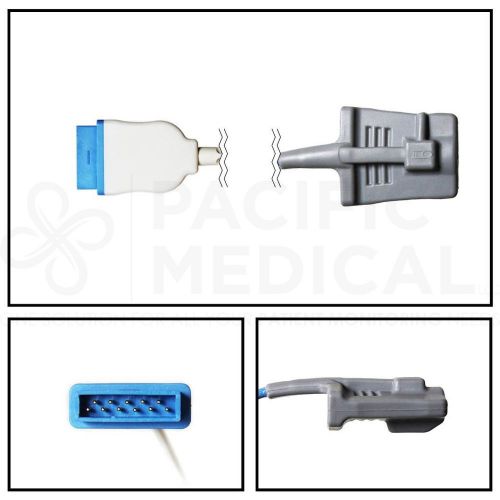

GE Datex-Ohmeda Hypertronics Adult Soft Shell SpO2 Sensor 10' Cable Yr Warranty

GE Datex-Ohmeda Marquette Adult Soft Shell SpO2 Sensor 10' Cable New Yr Warranty

GE Datex-Ohmeda Hypertonics Pediatric Soft Shell SpO2 Sensor 10' Cable Warranty

GE Marquette Adult Soft Shell SpO2 Sensor 10' Cable New Yr Warranty